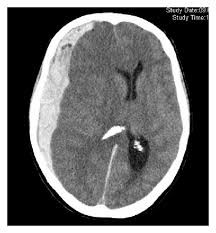

Ο όρος υποσκληρίδιο αιμάτωμα αναφέρεται στο αιμάτωμα που δημιουργείται στον υποσκληρίδιο χώρο του εγκεφάλου δηλαδή μεταξύ της σκληράς και της αραχνοειδούς μηνίγκας του εγκεφάλου. Το αιμάτωμα προέρχεται από τον τραυματισμό...